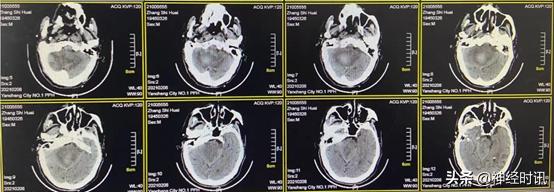

2月21日(脑血疏用药1个月后)复查CT,显示患者小脑血肿基本吸收消失,患者神志明显好转,可自主饮食,少量活动,继续服用脑血疏口服液

3月4日(脑血疏用药6周后)复查CT,显示患者小脑血肿已完全吸收,患者病情明显好转

4月7日(出院1月后)复查CT,显示患者小脑、脑干及脑室系统均已恢复正常